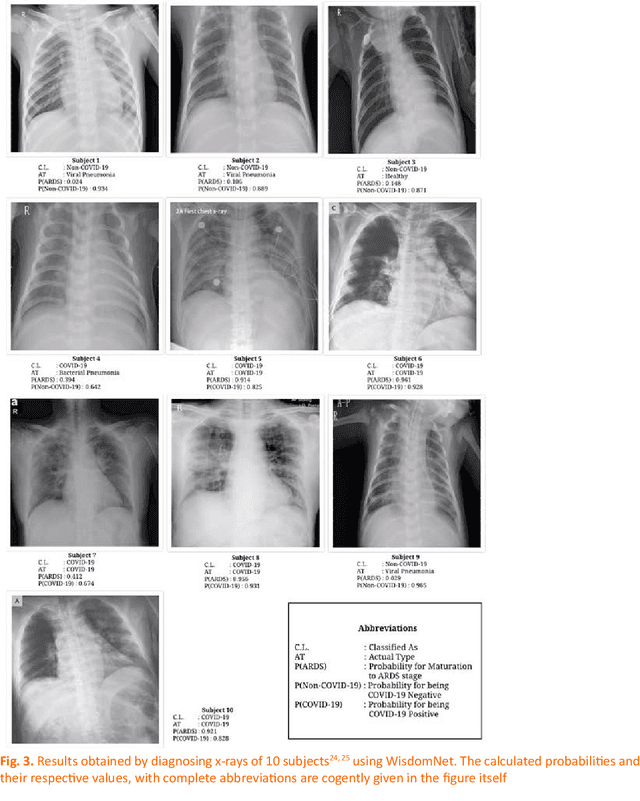

Abstract:Coronavirus is a large virus family consisting of diverse viruses, some of which disseminate among mammals and others cause sickness among humans. COVID-19 is highly contagious and is rapidly spreading, rendering its early diagnosis of preeminent status. Researchers, medical specialists and organizations all over the globe have been working tirelessly to combat this virus and help in its containment. In this paper, a novel neural network called WisdomNet has been proposed, for the diagnosis of COVID-19 using chest X-rays. The WisdomNet uses the concept of Wisdom of Crowds as its founding idea. It is a two-layered convolutional Neural Network (CNN), which takes chest x-ray images as input. Both layers of the proposed neural network consist of a number of neural networks each. The dataset used for this study consists of chest x-ray images of COVID-19 positive patients, compiled and shared by Dr. Cohen on GitHub, and the chest x-ray images of healthy lungs and lungs affected by viral and bacterial pneumonia were obtained from Kaggle. The network not only pinpoints the presence of COVID-19, but also gives the probability of the disease maturing into Acute Respiratory Distress Syndrome (ARDS). Thus, predicting the progression of the disease in the COVID-19 positive patients. The network also slender the occurrences of false negative cases by employing a high threshold value, thus aids in curbing the spread of the disease and gives an accuracy of 100% for successfully predicting COVID-19 among the chest x-rays of patients affected with COVID-19, bacterial and viral pneumonia.